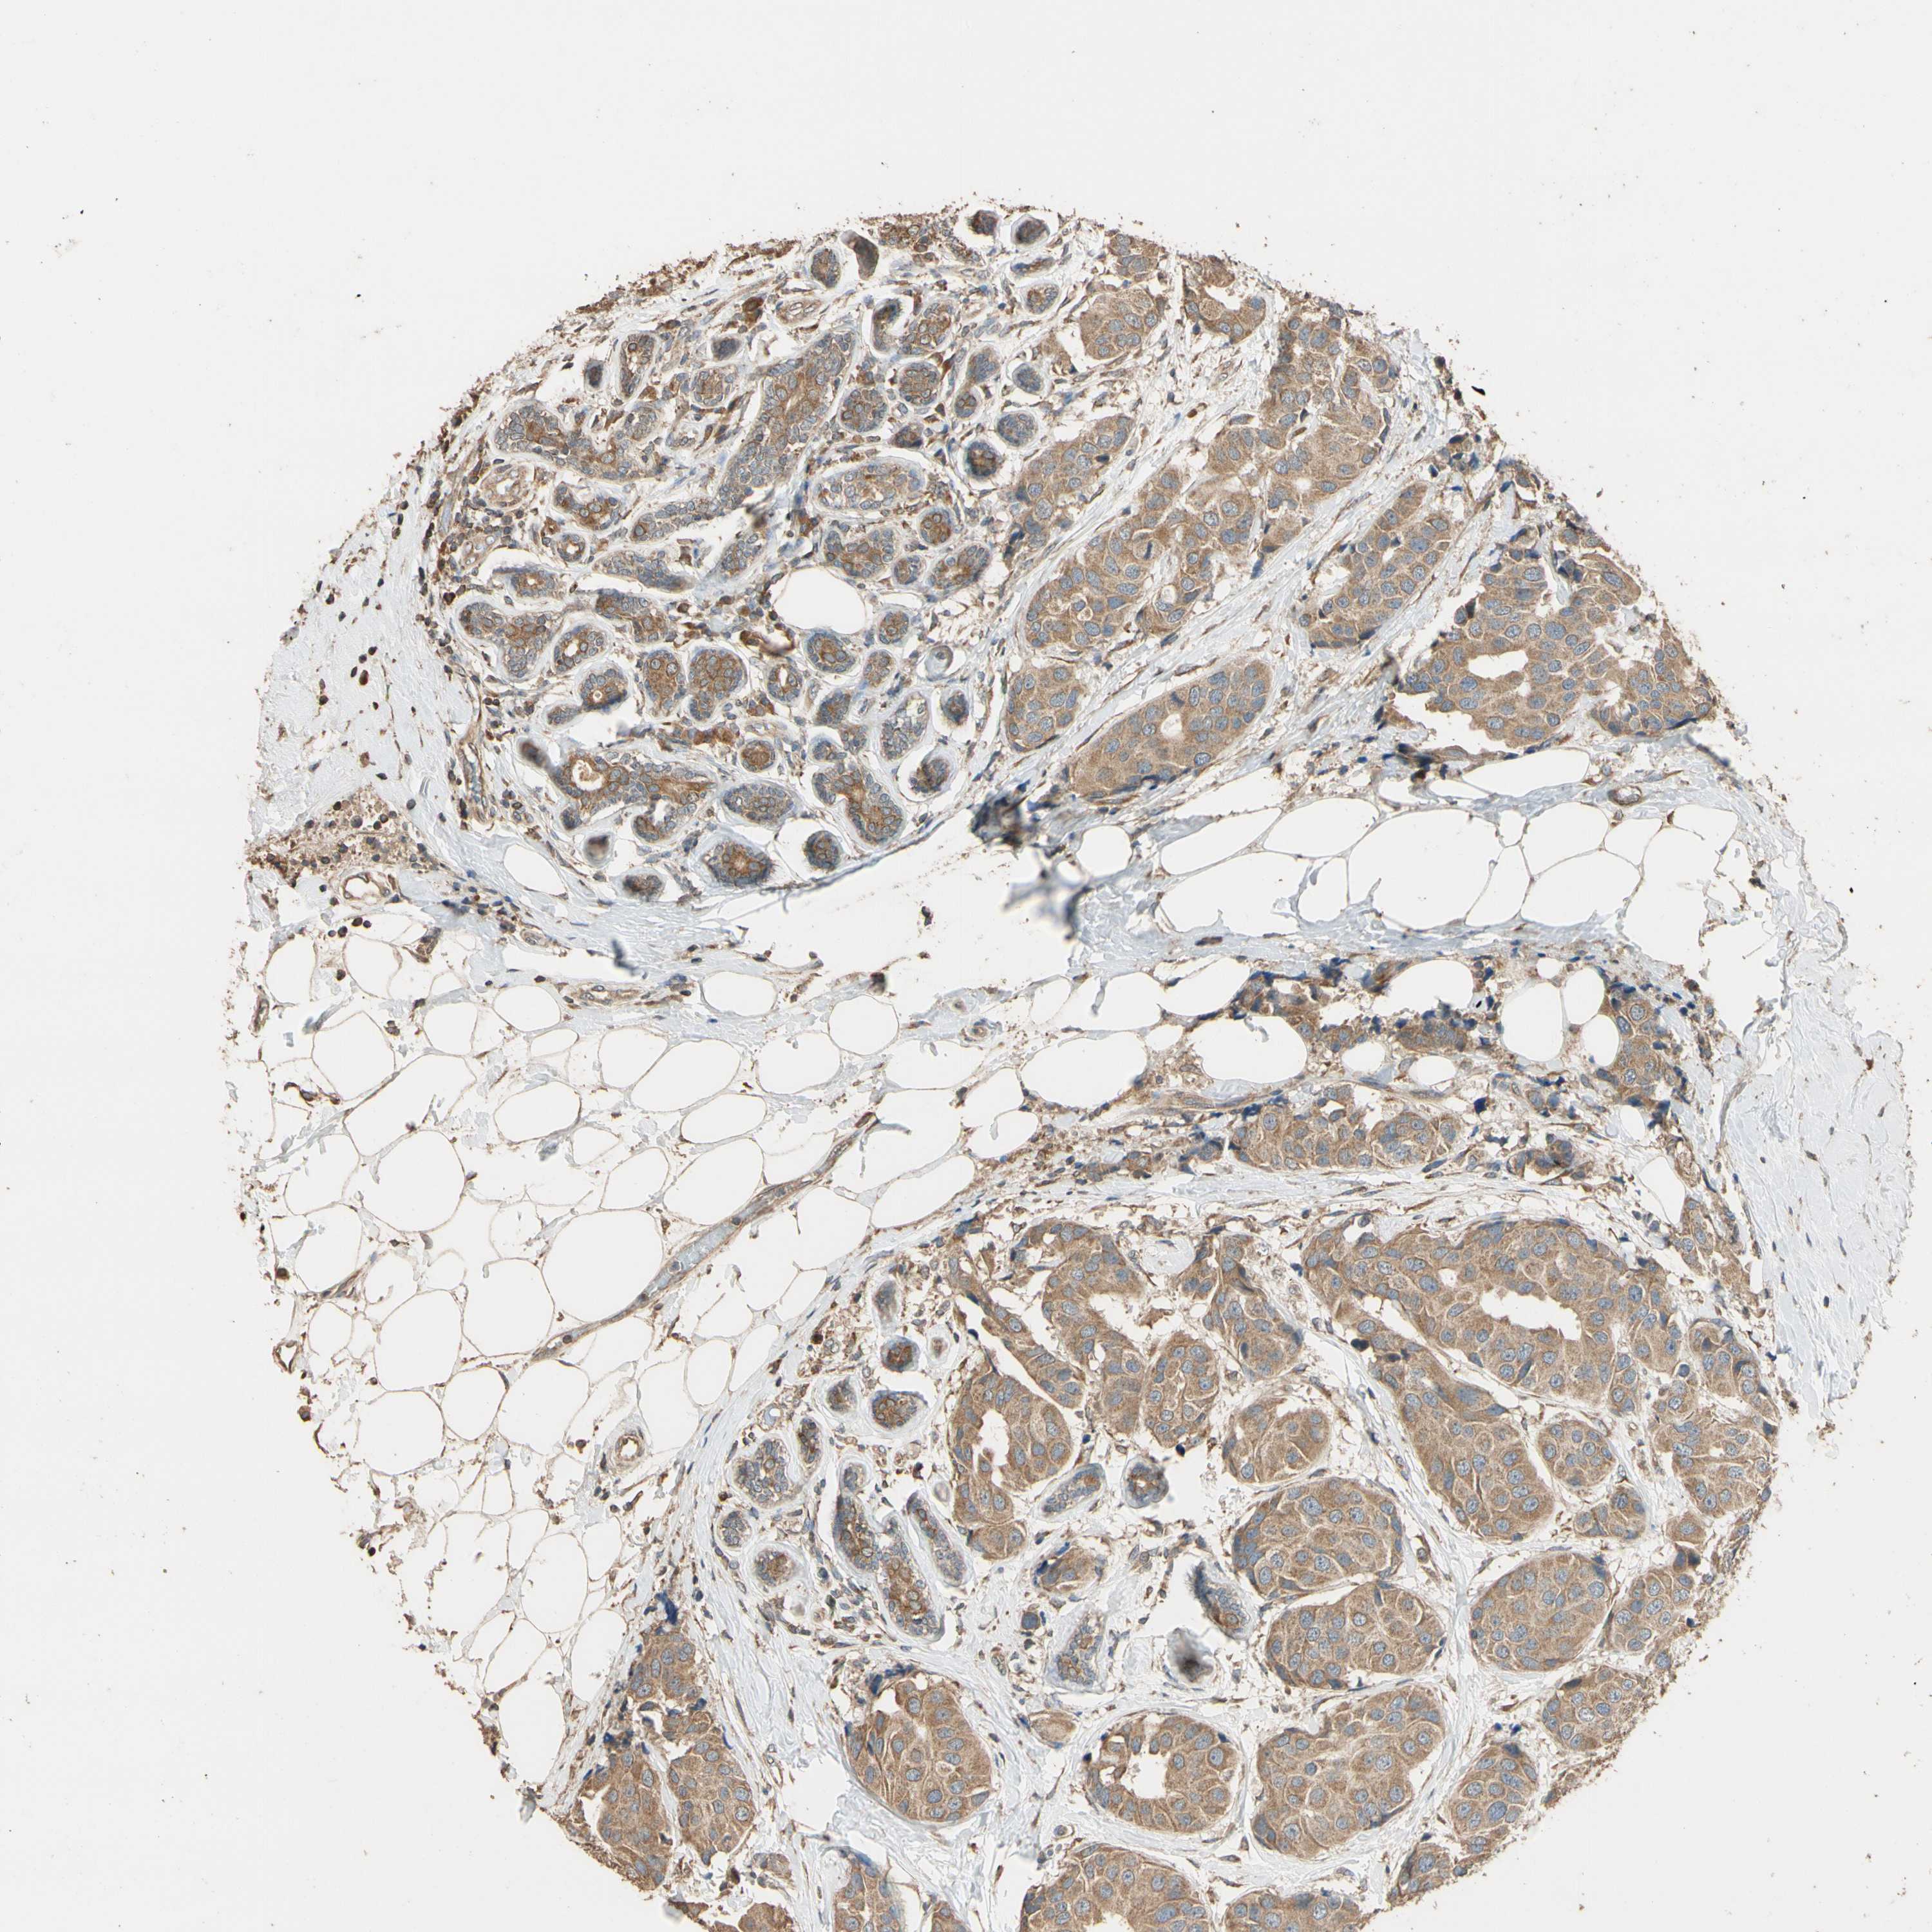

STX18

CANCER BREAST CANCER Show tissue menu

BRCA TCGA BRCA VALIDATION PROTEIN EXPRESSION

Breast cancer

Human cancer